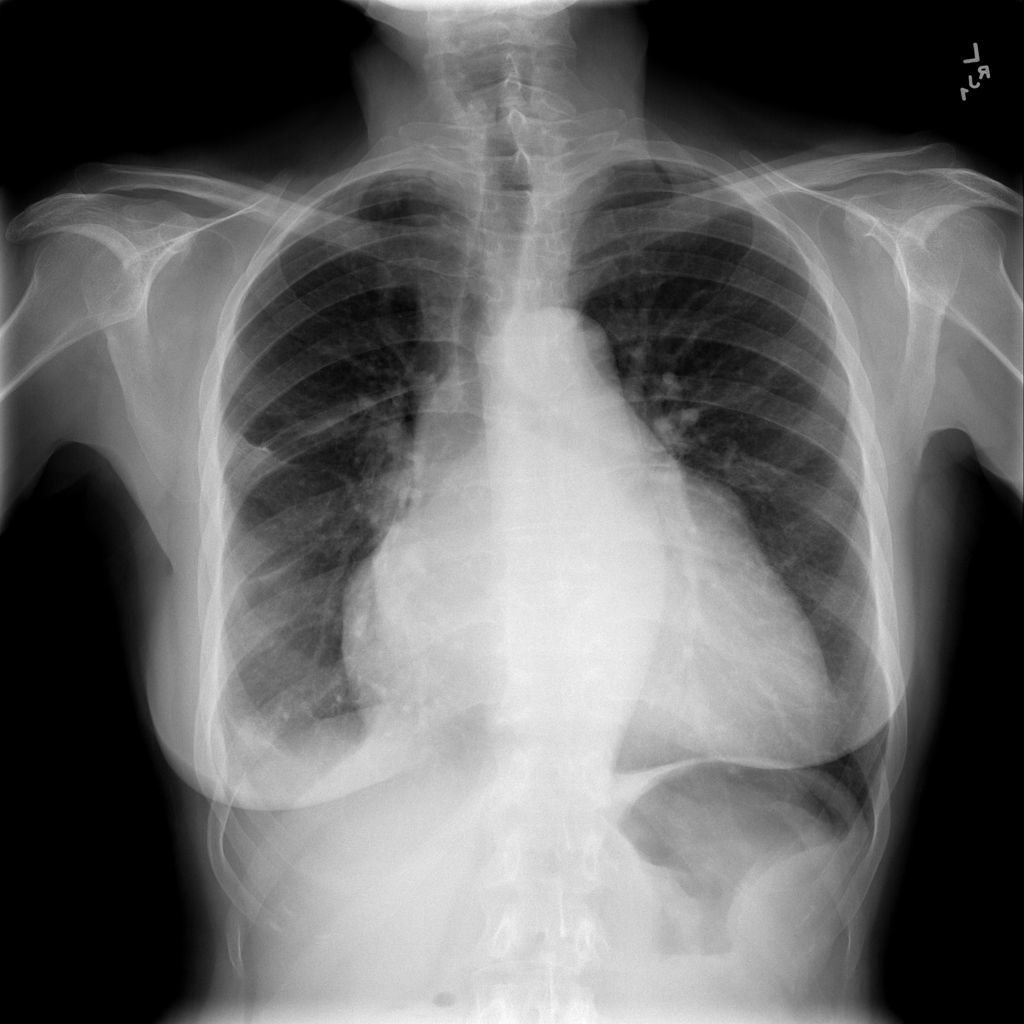

PAT-4639 · IMG-021Effusion

PAT-4639 · IMG-021

PA